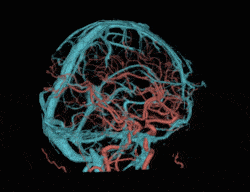

半秒单圈轴扫即可完成全脑扫描,多重软硬件技术克服锥束伪影和散射伪影挑战,提升软组织密度分辨率,改善颅底结构显示效果

3D打印精密工艺三维防散射栅格、Real 3D Full大锥角重建算法等多重硬件、软件技术协同,克服宽体探测器的核心技术挑战,天河640单圈扫描即可获得高质量的全脑、全冠脉轴扫图像